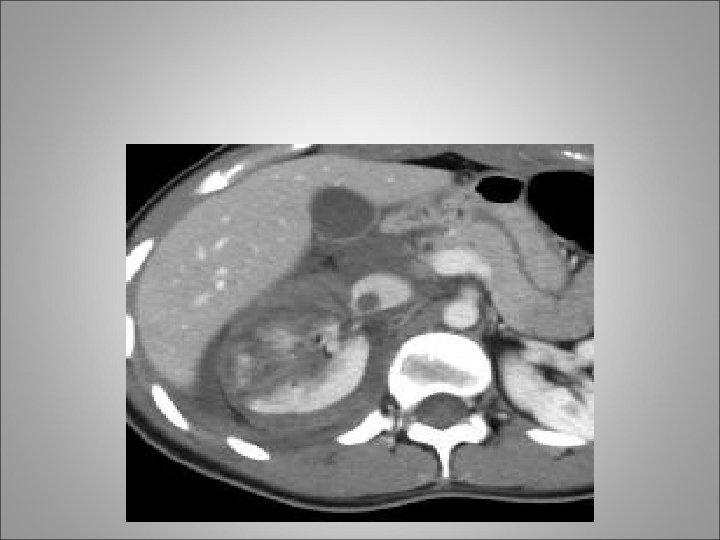

Renal Trauma • The pediatric kidney is believed to be more susceptible to trauma because of a decrease in the physical renal protective mechanisms • hematuria is very unreliable in determining who to screen for renal injuries • Indeed, some studies have failed to find any evidence of either gross or microscopic hematuria in up to 70% of children sustaining grade 2 or higher renal injury

Indications for Imaging • A significant deceleration or high-velocity injury such as one sustained in a high-speed motor vehicle accident, a pedestrian/bicycle-motor vehicle accident, a fall from more than 15 feet, or a strike to the abdomen or flank with a foreign object (e. g. , football helmet, baseball bat) • Significant trauma that has resulted in fractures of thoracic rib cage, spine, pelvis, or femur, or bruising of the torso/perineum, or signs of peritonitis • Gross hematuria • Microscopic hematuria (<50 red blood cells per highpowered field) associated with shock (systolic blood pressure less than 90 mm Hg) • penetrating injuries

Imaging • Single-Shot Intravenous Pyelography Is useful in the unstable patient requiring emergent laparotomy • Once the patient is stabilized in the operating room, single-shot intravenous pyelography (IVP) (2 m. L/kg intravenous bolus of contrast agent) with the radiograph taken 10 to 15 minutes after injection may be of benefit • Use of Arteriography is useful in patients with persistent or delayed hemorrhage which usually arises from the development of arteriovenous fistulas or pseudoaneurysm • Approximately 25% of patients with grade 3 to grade 4 renal trauma, managed in a nonoperative fashion, will develop persistent or secondary (delayed) hemorrhage • RGP +- DJ indications after renal trauma: (1) to rule out the presence of a partial/total ureteral disruption and (2) to aid in the management of a symptomatic urinoma

Renal pedicle injury Involving artery and vein With hematoma

Delayed imaging Injury to collecting system with extravasation

Delayed imaging Renal pelvis injury with leak of urine